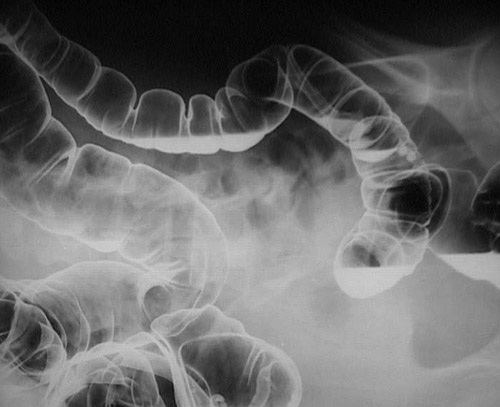

This barium enema demonstrates a pedunculated polyp on a long stalk in the descending portion of the colon.